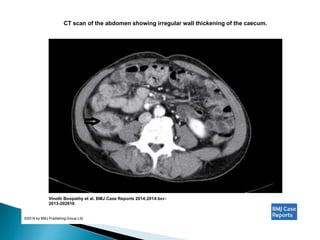

CT scan of the abdomen showing irregular wall thickening of the caecum.

Vinoth Boopathy et al. BMJ Case Reports 2014;2014:bcr-

2013-202616

©2014 by BMJ Publishing Group Ltd

CT scan ofthe abdomen showing irregular wall thickening of the caecum. Vinoth Boopathy et al. BMJ Case Reports 2014;2014:bcr- 2013-202616 ©2014 by BMJ Publishing Group Ltd